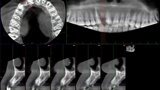

Esthetic Rehabilitation of Maxillary Anterior Teeth: Dr Sanjay Sah